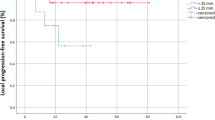

The search strategy identified 68 studies including 2457 patients treated with SBRT for central lesions. After repeated re-reading of each individual paper, 20 (30 %) studies with 608 (25 %) patients and 7 (10 %) studies with 207 (8 %) patients reporting ex negativo no specific and no long-term toxicity, respectively, were excluded. As a result, 41 (60 %) studies with 1642 patients (67 %) were considered to be highly relevant to the initial inquiry and included (see Fig. 1 and electronic supplementary material).